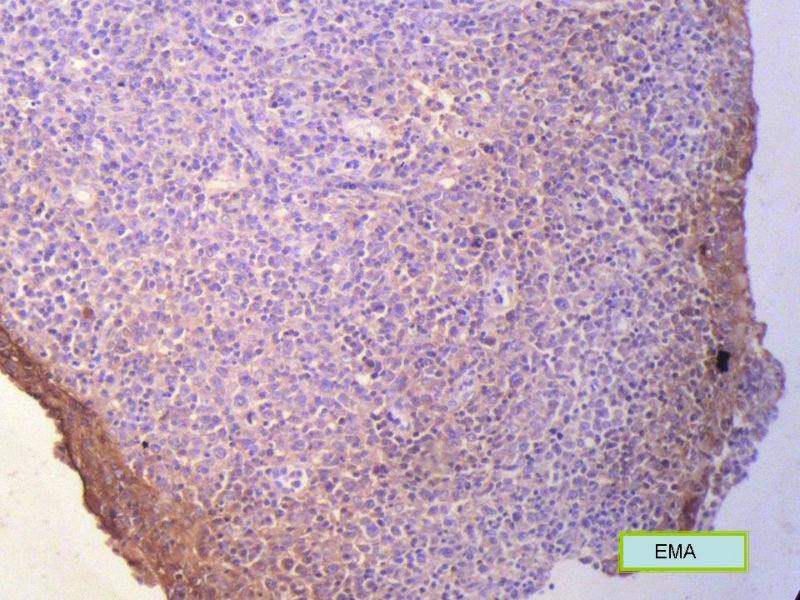

该患者可能存在病毒的感染,抑或是EB病毒的感染,包括CD30+的细胞在内,夹杂在组织细胞、小淋巴细胞之间的一些个大细胞是活化的淋巴细胞,表型看来属B细胞。整个形态呈反应性增生的形态。

总之,现有的图片显示的形态和IHC标记尚不足以诊断为淋巴瘤,除非有有基因重排的支持。

请看下图,显示的细胞比较杂,胞浆较丰富,胞核没有什么特别的异型性。没有促纤维增生反应和围血管生长表现,没有肿瘤性坏死,没有见到更多的核分裂,特别是病理性核分裂。因此认为,本例是淋巴组织反应性增生,可能是对病毒感染的反应。